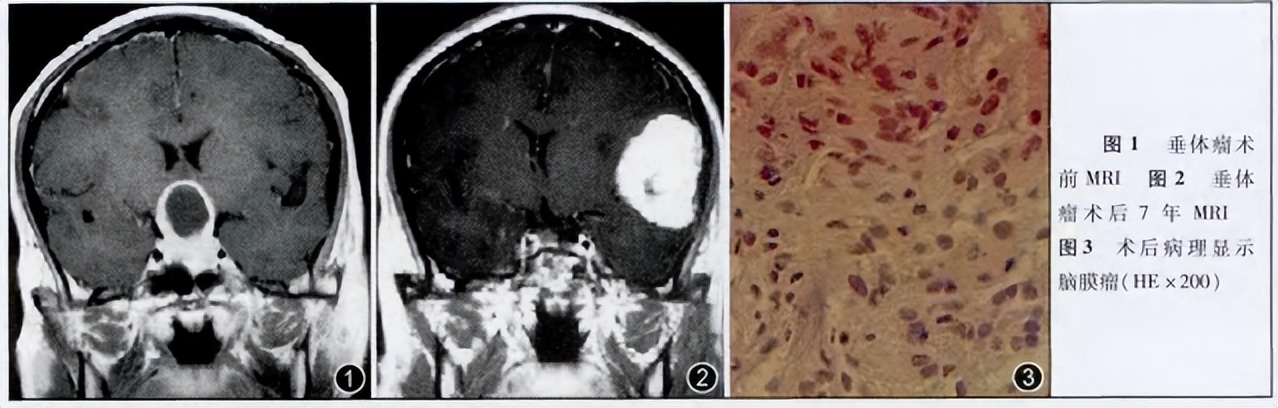

除了CA和脑膜瘤的生长有关联,也有相关案例表明脑肿瘤放疗也可能导致新发脑膜瘤生长,一名43岁的男性因突发剧烈头痛伴恶心呕吐送医治疗,7年前他曾因为催乳素垂体瘤行经鼻蝶窦手术,术后予于放疗。没想到CT及MRI检查后竟发现左颞叶脑膜瘤并卒中。新发的脑膜瘤和7年后的放疗治疗有关吗?